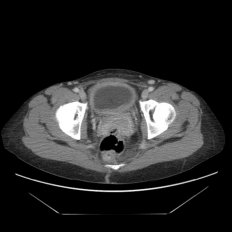

A pelvic ultrasound scan to check if any of the pelvic organs are compressing on your bladder to cause similar symptoms